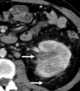

Congenital renal cystic disease